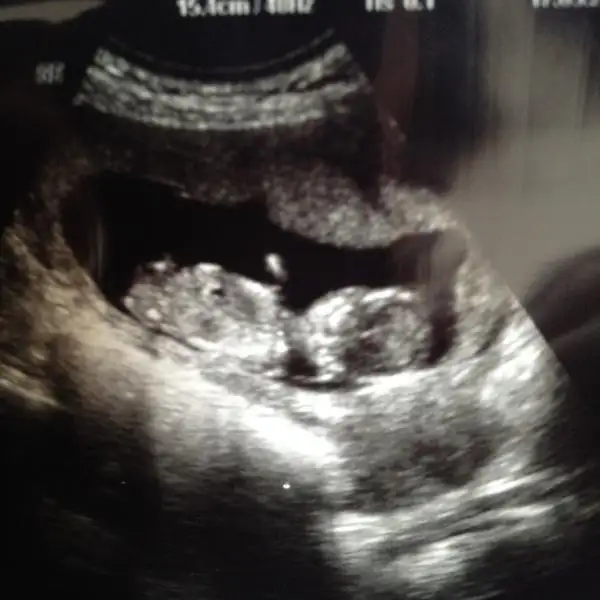

:bizimde 3.kızımız geliyormuş.zeynepcim yanılmapayıyla beraber erkege benzetmiştiniz.kısmette yokmuş olsun saglıklı olsun kurban olurum bunlara ben .rabbim tüm isteyenlerede versin inş.

Hayirli evlat olurlar ins en onemli sey onlarin saglikli olmalari dusuncelerin cok guzel annesi benimde ikinci kizim yolda bugun agrilarim var yarin gecmezse dr gidicem en buyuk korkum erken dogum uapmak onun kiz oldugnu ogrrndigimde icim burkulmadi dersem yalan olur ama suan hep dua ediyorum kuzum yeterki saglikla kucagima gelsin Allahim acisini gostermesin insanoglu iki meyvedende olsn istiyo tabiki ama en onemlisi Allah isteyen herkesi saglikli evlat sahibi yapsin onlarin imtihani daha zor iste bugun baya boyle seyler dusundum halimize sukurler olsun agrilarim duzensiz oluyo kasik ve belimde hic dr gtmek istemiyorum olmsuz bisi duymaktan korkuyorum heralde yengemiz erkn dogum yapti bebisi 1400gr dogdu sanirim bende etkilendim cok kendimi dinliyorum dualarinizda dogan bebisimize yer verirseniz cok sevinirim ins bian once iyi olur